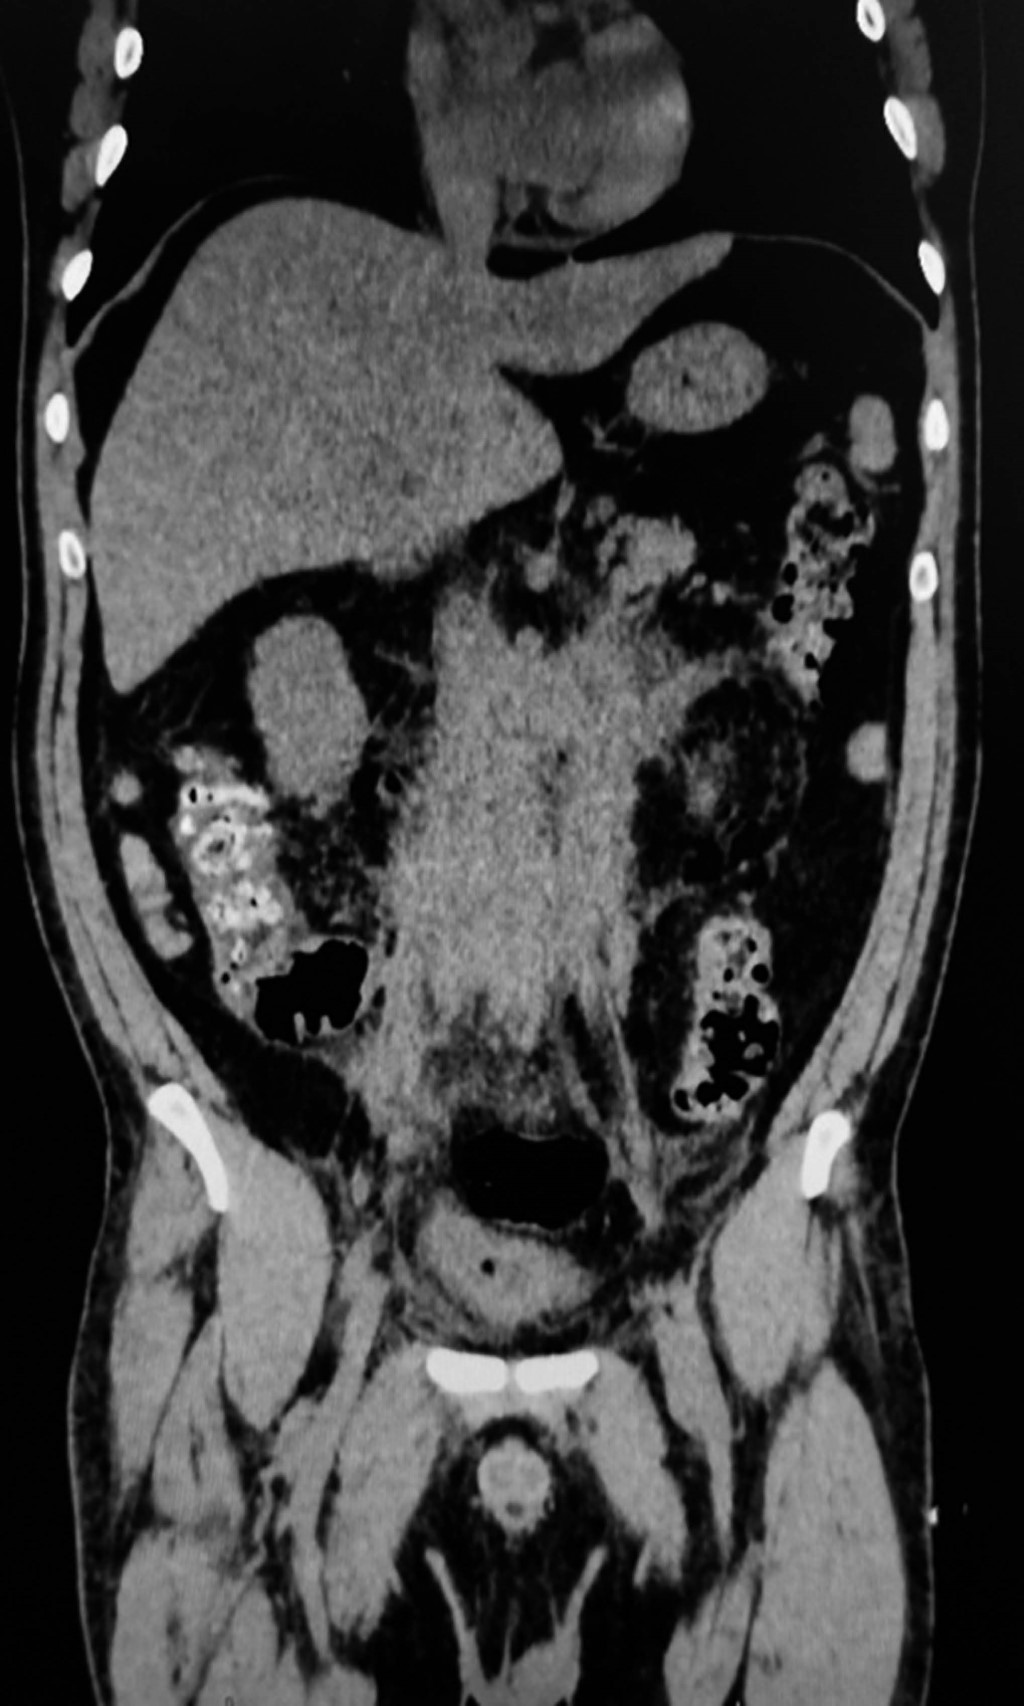

Figure 3